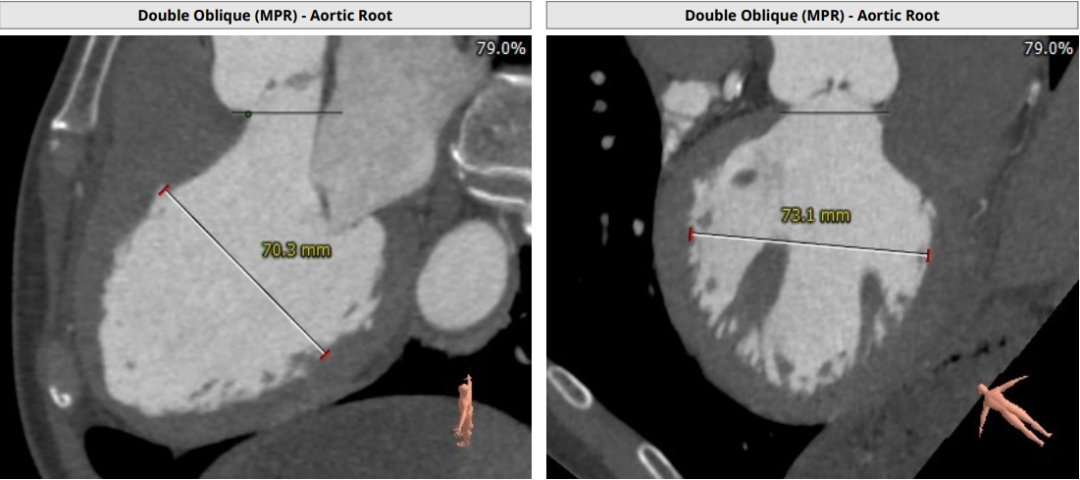

术前CT评估

Annulus Dimensions—25mm

LVOT—27.5mm

窦部:32.6*35.2*35mm

STJ—25.5mm

升主动脉存在明显增宽

重度主动脉瓣反流导致心室增大

患者为重度主动脉瓣反流,根部结构大,瓣叶菲薄,瓣膜锚定存在风险,结合病人整体主动脉根部结构,考虑使用启明医疗VenusA L29瓣膜进行植入。